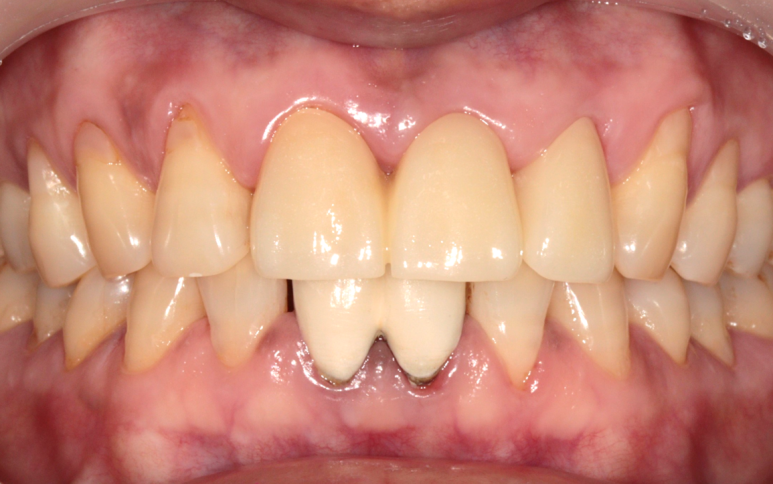

이후 보철 과정을 진행하였고,

다음과 같이 치료가 마무리되었습니다.

환자분께서는 치료 전 보철물보다 훨씬 예쁘다고 만족하셨네요.

좌측 2024. 1 - 우측 2024. 3